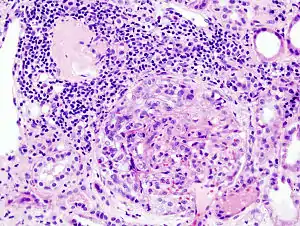

Histopathological image of crescentic glomerulonephritis in a person with MPO-ANCA positive rapid progressive glomerulonephritis. Hematoxylin & eosin stain.

It may occur as a result of anti-glomerular basement membrane disease, granulomatosis with polyangiitis, microscopic polyangiitis, lupus nephritis, IgA nephropathy, and following infection.[3] Diagnosis is based on blood tests, urine tests, and a kidney biopsy.[2] The biopsy show crescent-shaped scaring in over half the glomeruli.[3]